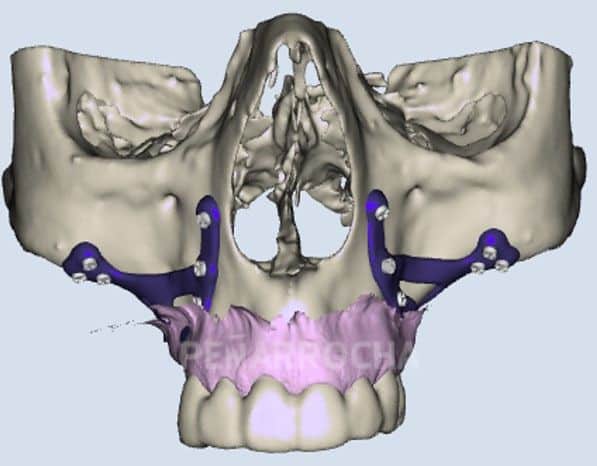

Implantes cigomáticos

Para los pacientes con una gran pérdida ósea en la parte posterior del maxilar, especialmente cuando la atrofia afecta a la zona posterior superior, los implantes cigomáticos pueden ser la solución.

Estos implantes se colocan en el hueso cigomático (hueso de la mejilla) en lugar de en el maxilar, lo que permite realizar una implantación sin necesidad de injertos óseos en casos extremos de atrofia.

Casos de éxito de implantes dentales con poco hueso en IDIM

En IDIM, contamos con más de 35 años de experiencia tratando casos complejos de implantología dental. A lo largo de nuestra trayectoria hemos logrado recuperar sonrisas de pacientes con condiciones óseas muy complicadas, incluida la falta de hueso suficiente para la colocación de implantes dentales.

Sabemos que la falta de hueso puede ser una preocupación importante, pero gracias a las técnicas avanzadas que utilizamos y a nuestro equipo especializado, hemos logrado devolver a nuestros pacientes no solo una sonrisa estética, sino también una funcionalidad óptima en su boca. Cada paciente es único, y por eso, nos centramos en ofrecer soluciones personalizadas para sus necesidades específicas, teniendo en cuenta la cantidad y calidad del hueso disponible.

Además, entendemos que antes de someterse a un tratamiento tan importante como los implantes dentales, es importante conocer otros casos de pacientes que hayan tenido experiencias satisfactorias. Por eso, a continuación, te compartimos algunos de nuestros casos de éxito más representativos de implantes dentales en pacientes con poco hueso: